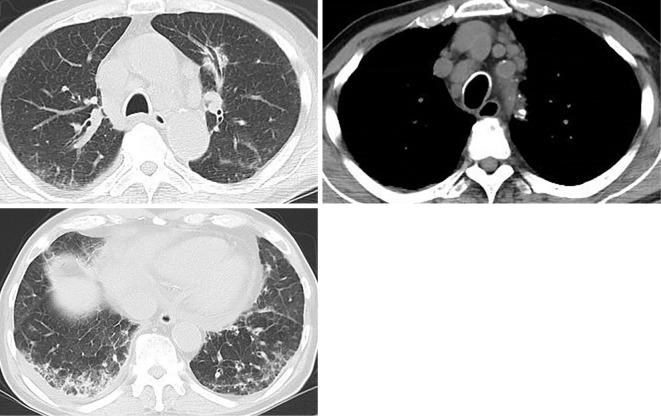

There are few cases describing the association of eosinophilia with hypercalcemia, and drug-induced eosinophilia with hypercalcemia has not been reported. A 74-year-old man had been diagnosed with asthma 4 months earlier. He was admitted due to eosinophilia with hypercalcemia. Chest computed tomography showed a nodule in the left lung and mediastinal lymphadenopathy. By obtaining a detailed medical history, clopidogrel was suspected as the prime cause of eosinophilia. After the discontinuation of clopidogrel, the eosinophilia with hypercalcemia, lung nodule and mediastinal lymphadenopathy improved. Clopidogrel-induced eosinophilia can potentially cause hypercalcemia. Obtaining a detailed clinical history is important in diagnosing the cause of eosinophilia.

目前仅有少数病例描述了嗜酸粒细胞增多与高钙血症之间的关联,而药物引起的嗜酸粒细胞增多与高钙血症尚未见报道。一名 74 岁男性在 4 个月前被诊断患有哮喘。他因嗜酸粒细胞增多伴高钙血症入院。胸部计算机断层扫描显示左肺结节和纵隔淋巴结病。通过详细询问病史,怀疑氯吡格雷是嗜酸粒细胞增多的主要原因。停用氯吡格雷后,嗜酸粒细胞增多伴高钙血症、肺结节和纵隔淋巴结病改善。氯吡格雷引起的嗜酸粒细胞增多可能导致高钙血症。详细的临床病史对于诊断嗜酸粒细胞增多的病因非常重要。